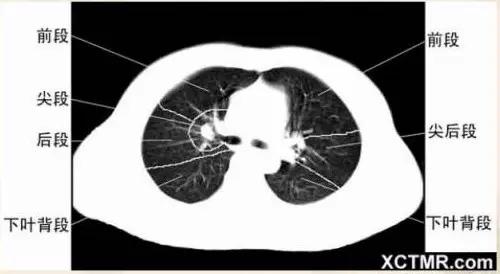

肺段划分